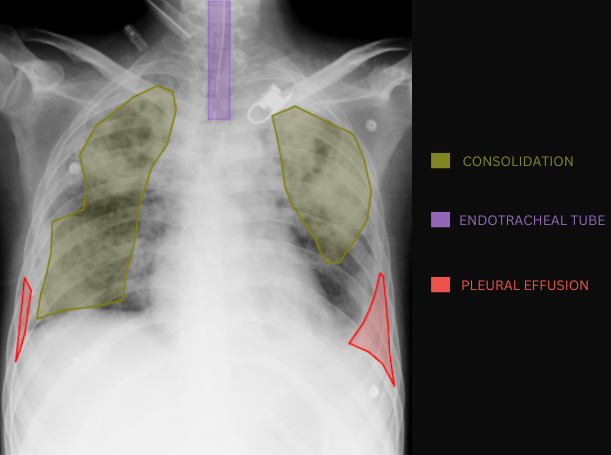

Chest X-ray with AI-detected pathology overlays showing consolidation, endotracheal tube, and pleural effusion annotations

What does AI-detected pathology look like?

Eight examples of AI-annotated chest X-rays with color-coded pathology overlays

Chest X-ray with AI-detected Consolidation highlighted

Consolidation

Chest X-ray with AI-detected Pleural Effusion highlighted

Pleural Effusion